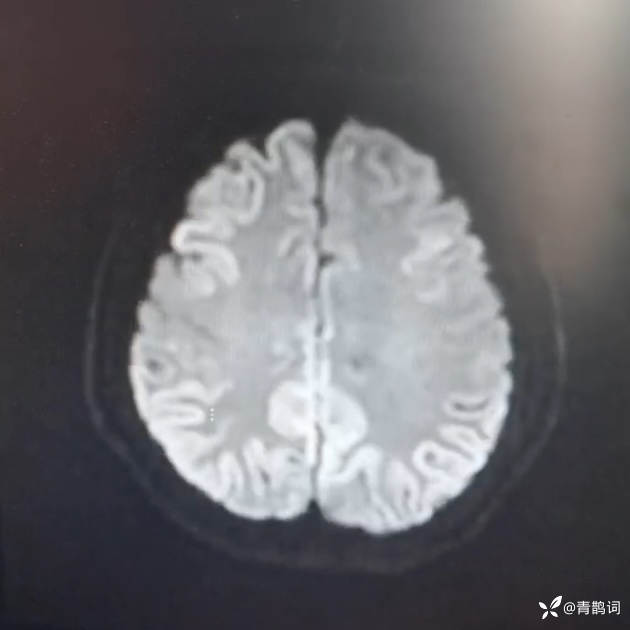

头部磁共振DWI及FLAIR: